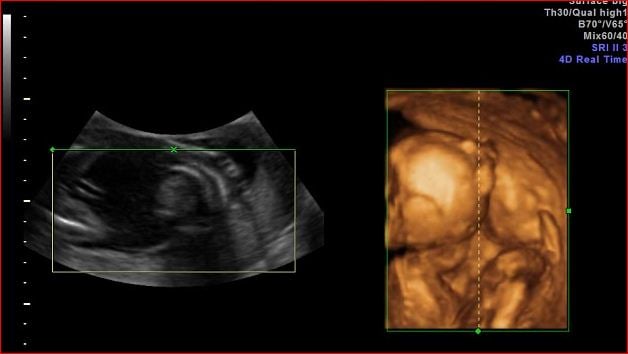

• Is the position of th baby in the 3D view is the equivalent position to the sonogram.  Any guess in the gender of baby?

• Hello new to this group. I was to impatient and went at 13 weeks and told maybe girl. Then 15 weeks boy. One looks obvious but the other is dots. What do you momma's think?

Hello new to this group. I was to impatient and went at 13 weeks and told maybe girl. Then 15 weeks boy. One looks obvious but the other is dots. What do you momma's think?

• Kgonzi said:

@Kgonzi‌ : the pictures aren't terribly good quality to be able to tell. The best I could guess is boy because it looks nothing like any female shots I've seen. That said, it's always a good idea to wait for your anatomy scan.

devthomas said:

Is the position of th baby in the 3D view is the equivalent position to the sonogram.  Any guess in the gender of baby?

I know this is a zombie thread but since everyone else is posting.....

What in gods name is this an ultrasound pic of? I've been staring at it for 5 minutes and cannot tell where baby is and what position.

Eta: damnit the pic didn't quote. The 3d one.